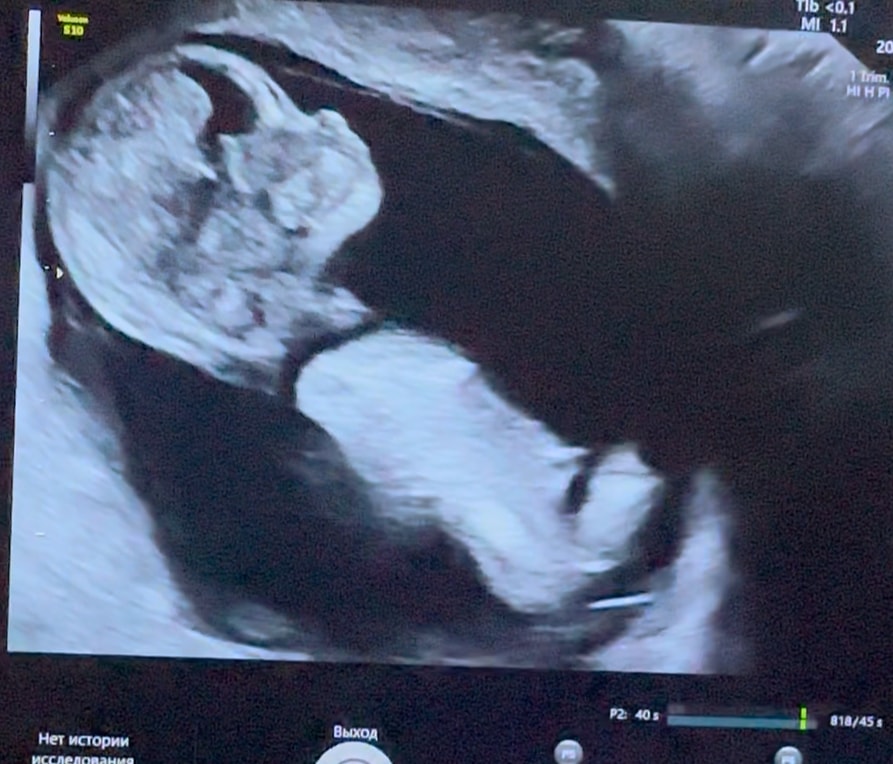

Ой а пуговка моя 🥰😍чудо ! Сосала ножки , ручки 😂 такая активная! ЧСС слава богу снизился 165! Дали снять видео 😍 фото жаль нет . От врача в восторге , даже пол сказал верно !)))